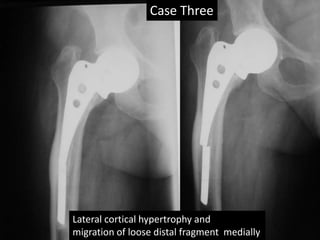

Case Three

Lateral cortical hypertrophy and

migration of loose distal fragment medially

• This old man had AMP left hip before 1992 (X-

rays)

• He had fracture trochanter on right side –

2000.

• DHS was done in 2000.

• Last follow up 2006.

• Rigid fixation by bone in fenestrations.

• Medial migration of distal loose piece.

Case Three Lateral corticalhypertrophy and migration of loose distal fragment medially

Case Three • Thisold man had AMP left hip before 1992 (X- rays) • He had fracture trochanter on right side – 2000. • DHS was done in 2000. • Last follow up 2006. • Rigid fixation by bone in fenestrations. • Medial migration of distal loose piece.